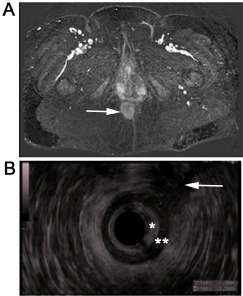

She underwent pelvic magnetic resonance imaging, which showed a heterogeneously enhancing soft tissue perianal mass with restricted diffusion. The lesion did appear to involve both the internal and external anal sphincters with invasion into the ischioanal fat. There were also mildly enlarged pelvic lymph nodes (Figure 2A).

On endoanal ultrasound, the mass appeared relatively hypoechoic with indistinct borders, with clear involvement of the external anal sphincter. Flexible sigmoidoscopy and endoscopic ultrasound were also performed to further evaluate the pelvic lymph nodes; cytology on fine needle aspiration was non-diagnostic (Figure 2B).

Figure 2: Imaging of perianal granular cell tumor involving external anal sphincter.

A) Magnetic resonance imaging of perianal granular cell tumor (white arrow). The tumor is a heterogeneously enhancing soft tissue mass with restricted diffusion which involves the sphincter muscles and invades ischioanal fat; B) Endoanal ultrasound of perianal granular cell tumor (white arrow). The mass is hypoechoic relative to surrounding ischioanal fat with indistinct borders. It involves the external anal sphincter (*indicates internal anal sphincter; **indicates external anal sphincter). View Figure 2

Imaging features of granular cell tumors tend to be nonspecific. CT scans show well-circumscribed soft-tissue masses that do not have calcifications. Ultrasound imaging of biliary GCTs reveals heterogeneous, mildly hyperechoic lesions that may have faint posterior shadowing [14]. Our endoanal ultrasound images showed the tumor to be heterogeneous and hypoechoic relative to surrounding ischioanal fat. On MRI, GCTs are heterogeneous with low signal intensity on T1 weighted images and high signal intensity on T2 weighted images [6].